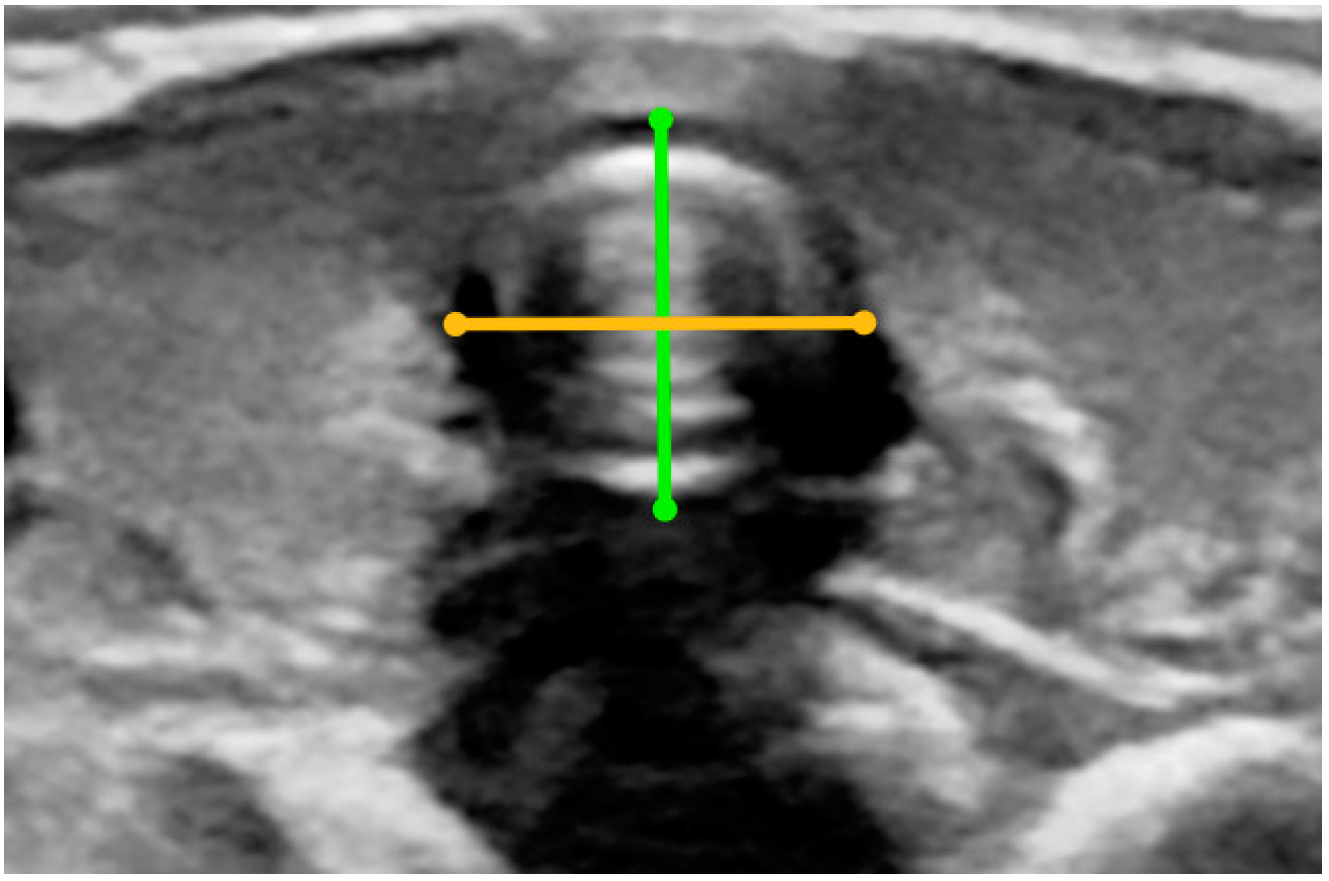

- Width and depth of the trachea (measurement taken in the transverse plane of the longest transverse dimension of the trachea from the external edges of the tracheal cartilages and measurement of the longest depth of the trachea from the external margin of the tracheal cartilage to the outer part of the membranous wall) (Figure A10);